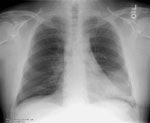

The patient was treated with a course of antibiotics with some clinical improvement, but a follow-up chest radiograph demonstrated that the infiltrate had enlarged and appeared mass-like.